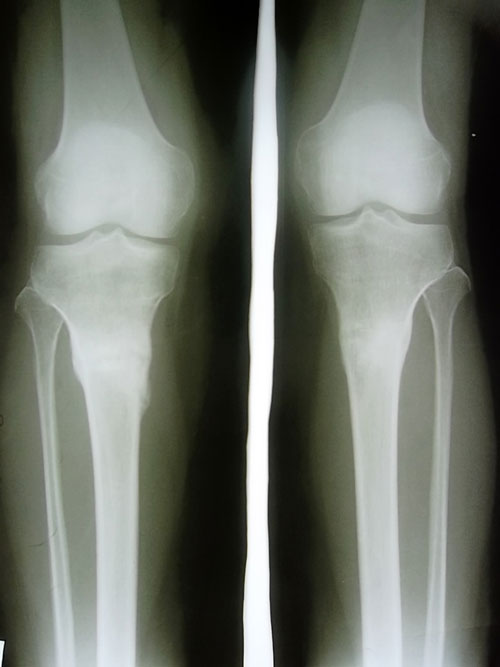

рентген в 1,5 месяца после снятия аппаратов.

Сращение отличное, живи без ограничений! d6c695c748.gif

Вложения

SAM_6481.JPG

SAM_6479.JPG